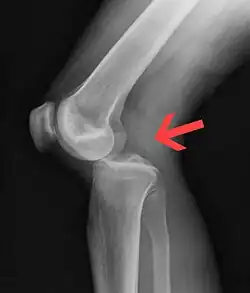

Plain lateral X-ray of the left knee showing a posterior knee dislocation[1]